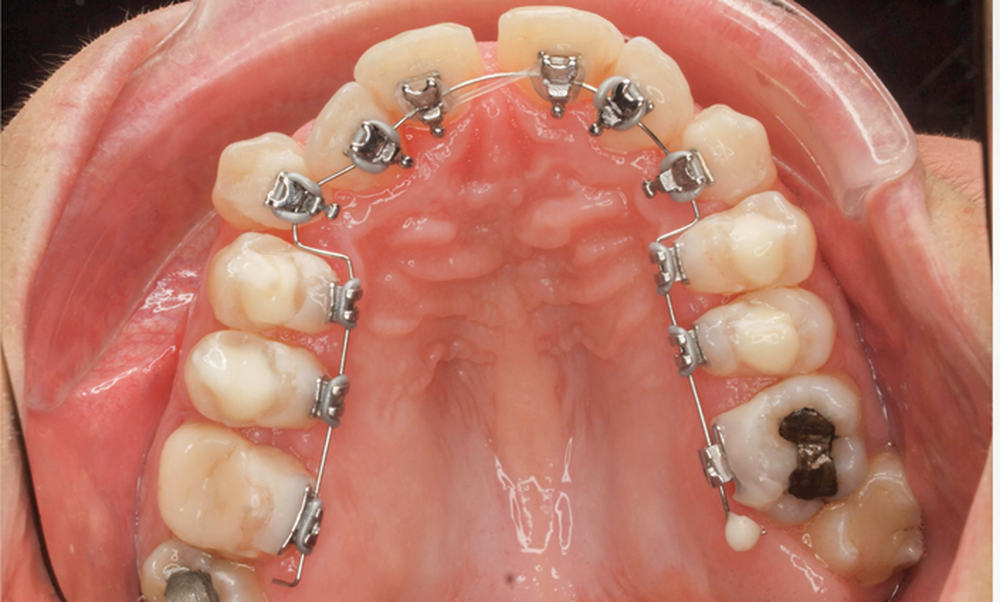

- Troisième rendez-vous (fig. 2c) : les arcs NiTi .014 sont religaturés pour améliorer le nivellement-alignement.

- Quatrième rendez-vous (fig. 2d) : des arcs TMA .017 x .017 sont posés. Les premières et deuxièmes molaires sont collées en vestibulaire avec un arc sectionnel NiTi 0,019×0,025.

- Cinquième rendez-vous (fig. 2e) : des arcs TMA .017 x .025 sont posés et des tubes linguaux collés sur 17 et 27 pour le port d’élastiques criss-cross nocturnes.

- Sixième rendez-vous (fig. 2f) : les cales sont déposées. Un pliage de finition sur 21 est réalisé pour améliorer son angulation.

- Septième rendez-vous : les appareils sont déposés. Une empreinte numérique est prise pour réaliser trois aligneurs afin de parfaire le résultat occlusal et esthétique (fig. 3a-h).